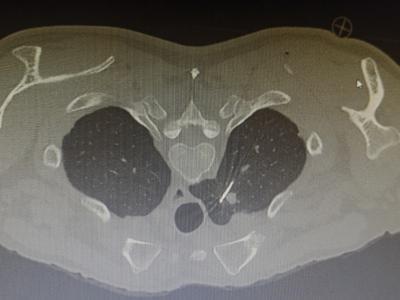

1.精准定位:医生通过CT影像锁定肿瘤位置,像导航一样精准规划“进攻路线”。

2.细针穿刺:用一根比笔芯还细的针,避开重要血管和器官,直达肿瘤“老巢”。